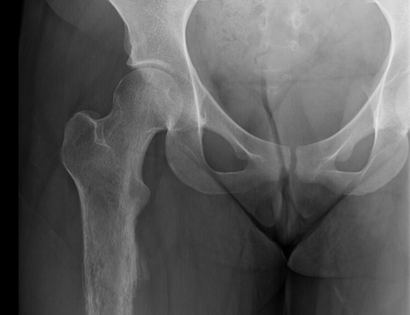

Proximal Femur Xray Photo Tumor

This is an x-ray of the femur prior to surgery. The tumor is located on in the entirety of the femur bone seen in the photo.